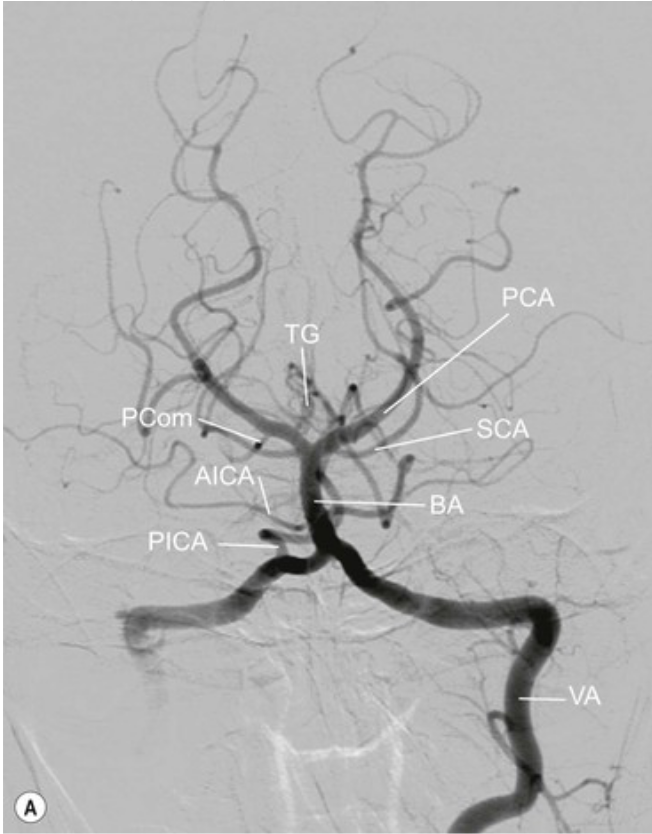

20.1 Patient presents with hemisensory loss and right homonymous hemianopia. Which vessel is affected?

a. Anterior communicating artery

b. Posterior cerebral artery

c. Posterior inferior cerebellar artery

d. Vertebral artery

e. Basilar artery

REPEAT

PCA Contralateral